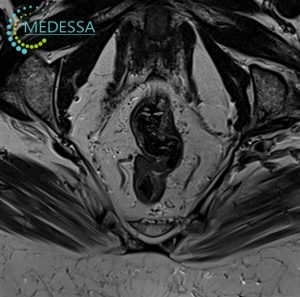

Magnetic Resonance Imaging (MRI) of internal organs is a modern non-invasive diagnostic method that allows detailed visualization of organs, tissues, and anatomical structures without surgery or radiation exposure.

Due to its high diagnostic accuracy, MRI can detect even minor tissue changes, which is crucial for the early identification of tumors, inflammatory processes, and other abnormalities.

Pelvic MRI

For women:

- Lower abdominal or pelvic pain.

- Menstrual irregularities.

- Suspected endometriosis, fibroids, ovarian cysts.

- Infertility.

- Preoperative gynecological assessment.